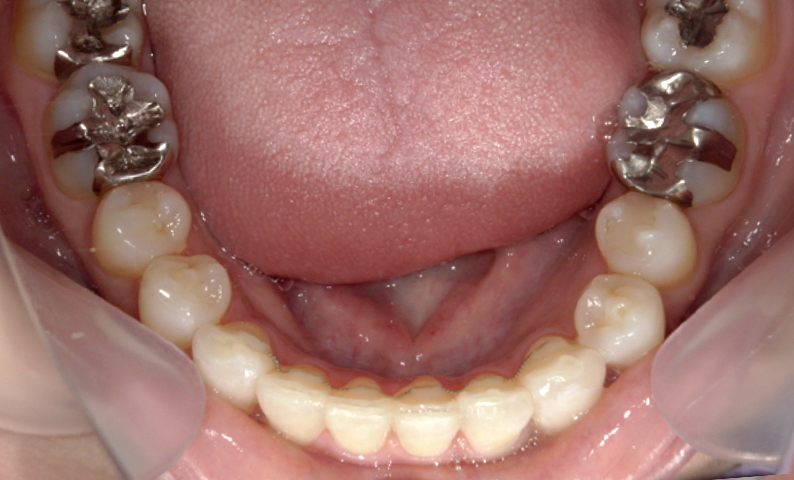

症例:上下顎の部分矯正

症例_002 前歯「捻転歯」症例

治療期間:10ヶ月金額:54万円+税30代女性少しのねじれ捻転歯前歯の突出感